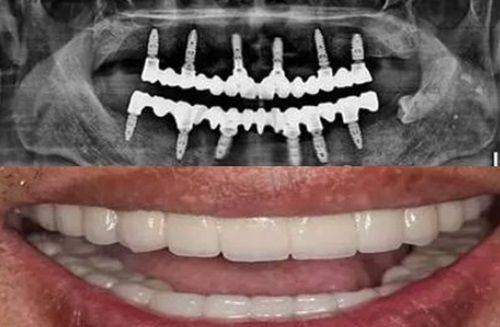

数字化种植牙是诊所的又一特色项目。利用数字化技术,医生可以更精细地进行种植手术,缩短手术时间,减少患者的痛苦,提高种植牙的成功几率和稳定性。

数字化种植牙设备也是诊所的一大亮点。通过数字化技术,医生可以在术前进行精细的规划,模拟种植过程,确保种植体的位置和角度更加正确,提高种植牙的稳定性和成功几率。